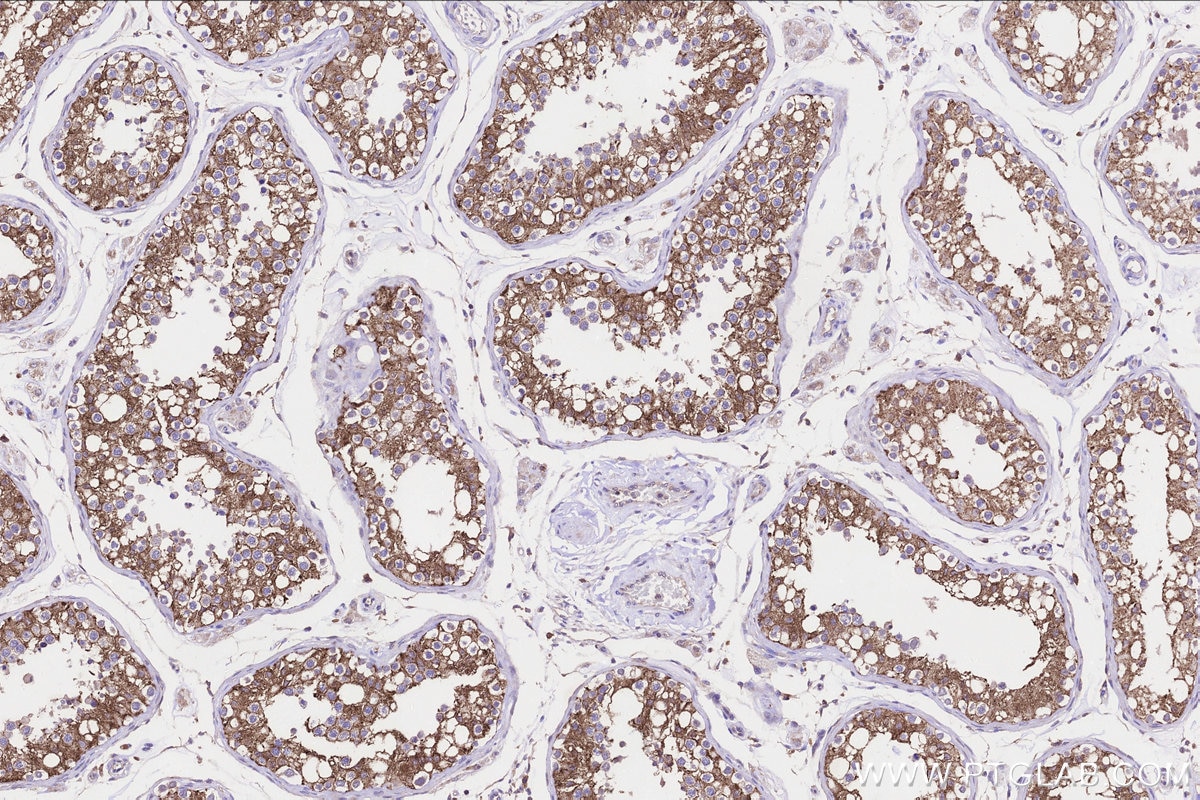

| Positive IHC detected in | human testis tissue Note: suggested antigen retrieval with TE buffer pH 9.0; (*) Alternatively, antigen retrieval may be performed with citrate buffer pH 6.0 |

| Immunohistochemistry (IHC) | IHC : 1:250-1:1000 |

23809-1-AP targets FATE1 in WB, IHC, ELISA applications and shows reactivity with human, mouse samples.

FATE1 ,also named as Fetal and adult testis expressed transcript protein, express predominantly in testis, with some expression in lung, heart, kidney, adrenal gland and whole brain. FATE might represent a novel target gene of SF-1 in testicular differentiation and germ cell development. FATE1 also involves in the regulation of a wide variety of cellular processes ,including the cell cycle, immune responses, signaling cascades and developmental events through target proteins, such as cyclins, cyclin-dependent kinase inhibitors.